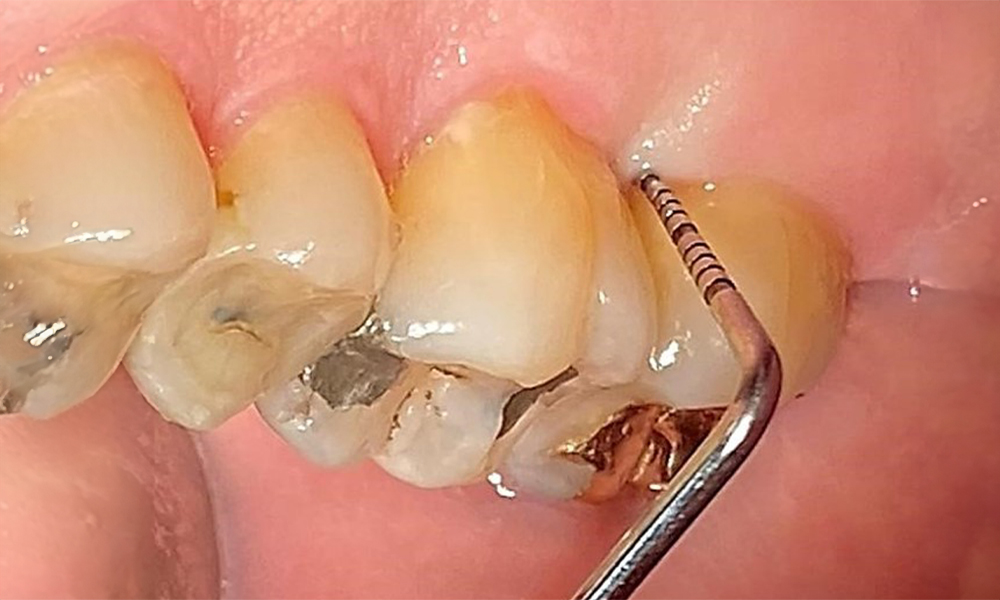

Сондиране за документиране на резултатите медиопалатинално на зъб 27.

Фиг. 8: Сондиране за документиране на резултатите медиопалатинално на зъб 27. © д-р Р. Крапф

Няма ограничения по отношение на избора на методи за измерване. Редовната супрагингивална и субгингивална инструментация е от съществено значение за предотвратяване на прогресията на заболяването поради вече съществуващия пародонтит и високия риск от рецидив. От общомедицинска гледна точка няма ограничения върху избора на инструменти за механично отстраняване на биофилм и отстраняването трябва да се извършва според нуждите. Твърдата и минерализирана плака, като зъбен камък и конкременти, трябва да се отстранява с помощта на ръчни инструменти или ултразвукови скалери (фиг. 9) (8, 9).

Използване на ултразвуков накрайник за отстраняване на твърда минерализирана плака (скалер Proxeo Ultra с перио накрайник, W&H).

Фиг. 9: Използване на ултразвуков накрайник за отстраняване на твърда минерализирана плака (скалер Proxeo Ultra с перио накрайник, W&H). © д-р Р. Крапф